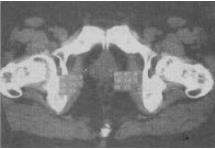

- 单项选择题 患者,男,63岁,排尿困难1个月余,加重伴血尿10天。PSA为43ng/mL。CT表现见图,最有可能是哪种疾病()。

C、前列腺癌